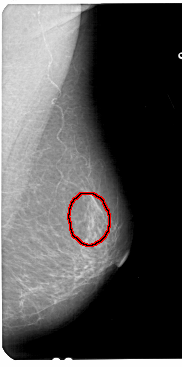

A_1433_1.RIGHT_MLO

LEFT_MLO LINES 5491 PIXELS_PER_LINE 2671 BITS_PER_PIXEL 12 RESOLUTION 43.5 NON_OVERLAY

FILE: A_1433_1.RIGHT_MLO.OVERLAY

TOTAL_ABNORMALITIES 1

ABNORMALITY 1

LESION_TYPE CALCIFICATION TYPE PUNCTATE DISTRIBUTION SEGMENTAL

ASSESSMENT 2

SUBTLETY 3

PATHOLOGY BENIGN

TOTAL_OUTLINES 1

BOUNDARY